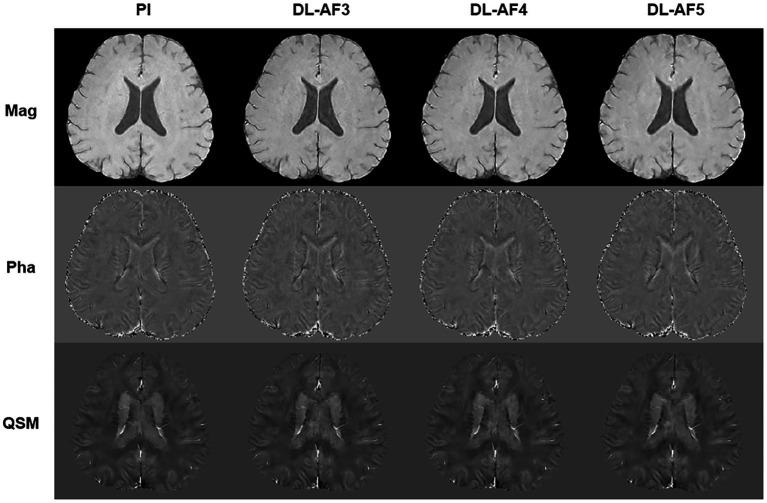

Participants were scanned with both parallel imaging (PI)-QSM and DL-QSM methods. The PI- and DL-QSM scans had identical imaging parameters other than acceleration factors (AF). The DL-QSM employed Poisson disk style under-sampling scheme and a previously developed cascaded CNN based reconstruction model, with acquisition time of 4:35, 3:15, and 2:11 for AF of 3, 4, and 5, respectively. For PI-QSM acquisition, the AF was 2 and the acquisition time was 6:46. The overall image similarity was assessed between PI- and DL-QSM images using the structural similarity index (SSIM) and peak signal-to-noise ratio (PSNR). QSM values from 7 deep brain nuclei were extracted and agreements between images with different Afs were assessed. Finally, the correlations between age and QSM values in the selected deep brain nuclei were evaluated.

59 participants were recruited. Compared to PI-QSM images, the mean SSIM of DL images were 0.87, 0.86, and 0.85 for AF of 3, 4, and 5. The mean PSNR were 44.56, 44.53, and 44.23. Susceptibility values from DL-QSM were highly consistent with routine PI-QSM images, with differences of less than 5% at the group level. Furthermore, the associations between age and QSM values could be consistently revealed.